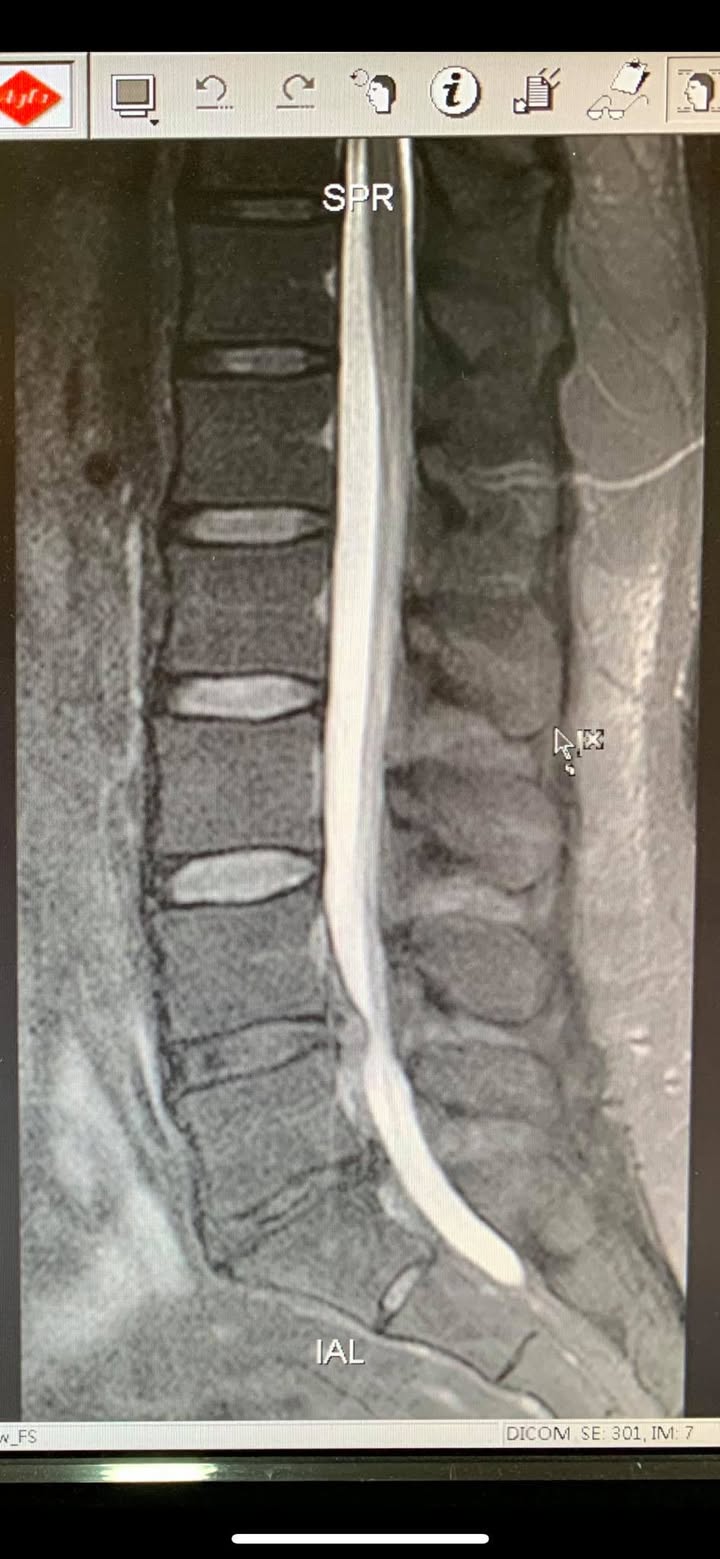

Cervical Spine Treatment Cases 腰椎治療案例 史上超多內心小劇情醫案文章請耐心看完 辛苦的貨車司機腰椎辛酸血淚史 各式各樣治療都... 2020.04.24 感謝台中后里區鍾小姐熱情見證 車禍後導致椎間盤突出 痛到懷疑人生原本考慮開刀治療 ... 2020.04.16 #腰椎滑脫合併椎管狹窄醫案 #脊椎整合中醫微創逆轉勝 #老人家不可以跌倒不可以跌到 #... 2020.04.11 #搬重物閃到腰受傷一痛就痛兩年 #復健許久沒效拍攝核磁共振才知道椎間盤突出 #脊椎整... 2020.04.10 #抱狗閃到腰居然痛麻到不行快半年 #原來是椎間盤突出啊 #脊椎整合中醫微創逆轉勝 2020.04.03 #腰椎滑脫逆轉勝醫案 #曾經大痛到一個月無法走路居家臥床 #原本認真考慮接受骨科融合... 2020.03.31 #腰椎輕微滑脫醫案 #感謝桃園八德蔡阿姨熱情見證 #脊椎整合中醫微創 2020.03.20 腰痛到小腿一直麻痛是怎麼回事 腰椎第四第五椎間盤突出惹禍 打噴嚏跟咳嗽都超痛的 脊... 2020.03.11 #腰椎明顯滑脫醫案 #感謝三重蔡先生熱情見證 #曾經大痛到無法工作跟無法睡覺 #脊椎整... 2020.03.07 #感謝雲林李阿姨熱情見證 #腰椎滑脫合併椎管狹窄 #脊椎整合中醫微創療法逆轉勝 2020.03.01 曾經腰痛連大腿小腿到無法睡覺 大醫院核磁共振檢查後證實椎間盤突出 四個多月的疼痛原... 2020.03.05 #跨國治療台灣醫療奇蹟 #遠從澳洲坐飛機回台專門接受治療 #台灣中醫脊椎整合微創療法... 2020.01.17 #兒子老婆陪同林伯伯一起見證奇蹟 #腰椎滑脫合併椎管狹窄 #治療前走路無法超過五分鐘 ... 2019.12.28 #跨國治療台灣醫療奇蹟 #遠從越南坐飛機專門接受治療 #台灣中醫脊椎整合微創療法立大... 2019.12.26 再度逆轉勝!腰椎治療醫案 原本痛到懷疑人生都想去手術了 八週治療後生路活虎!還可以... 2019.12.18 ← 上一頁 11 12 13 14 15 下一頁 →